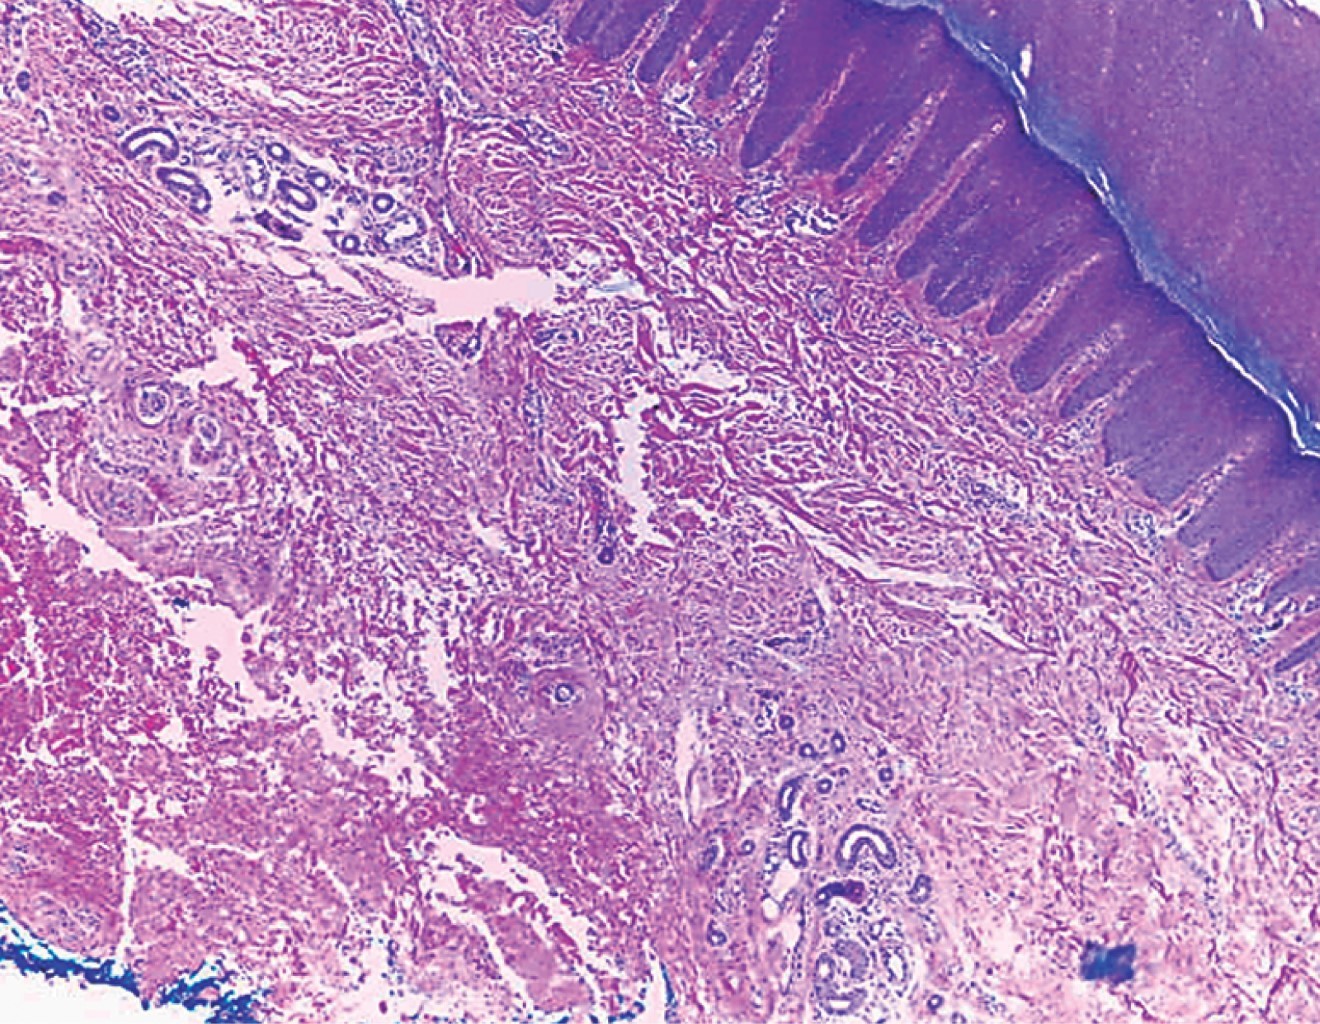

Vascular anomalies are abnormalities that are caused by errors during vascular genesis, which encompass a variety of disorders. They are anomalies that are usually present at birth and may become evident late on in life. Vascular anomalies in the hand, specifically in the fingers, are frequently underdiagnosed; these alterations are confused with congenital malformations in children and a history of trauma or vascular procedures in adults. We present a case of 35-year-old man, with a 1 cm subcutaneous mass in the III extensor zone of the second finger of the right hand, at the proximal interphalangeal joint. The mass that had not caused pain, had been present for three years with no major size changes. Pathology revealed an arteriovenous malformation with no signs of malignancy.

Figure 1